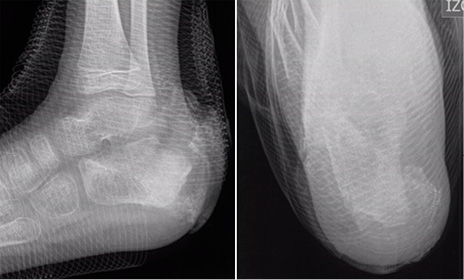

La radiografía convencional fue examen de rutina en todos los pacientes del estudio. Evidenció hallazgos inespecíficos en 5 de 9 pacientes consistentes en edema de tejidos blandos. En uno de esos casos se apreciaron lesiones óseas en el calcáneo (Figura 1). La TC se utilizó como complemento en un caso para confirmar un defecto óseo cortical secundario a la infección (Figura 2).

Figura 1. Radiografía en paciente de 5 años con osteomielitis de calcáneo polimicrobiana. Se aprecia aumento de la opacidad ósea acompañada de resorción en la región posterior del calcáneo, con edema de tejidos blandos. Imágenes propias de los autores.